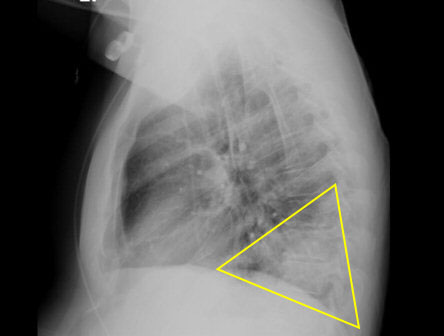

chest x-ray

Test

To evaluate for lobar infiltrate. If infiltrate is absent, but clinical suspicion remains, laboratory tests should be ordered. [Figure caption and citation for the preceding image starts]: Chest x-ray showing Legionella infection: right lower lobe infiltrate consistent with pneumonia (arrow). Legionella confirmed positive with urinary antigen testFrom the personal collection of Dr Forest W. Arnold; used with permission [Citation ends].

[Figure caption and citation for the preceding image starts]: Chest x-ray (lateral) showing infection: posterior segment of lower lobe consistent with pneumonia; the area in the triangle is normally clear (black). confirmed with positive urinary antigen testFrom the personal collection of Dr Forest W. Arnold; used with permission [Citation ends].

Result

Legionnaires' disease: lobar infiltrate; Pontiac fever: normal